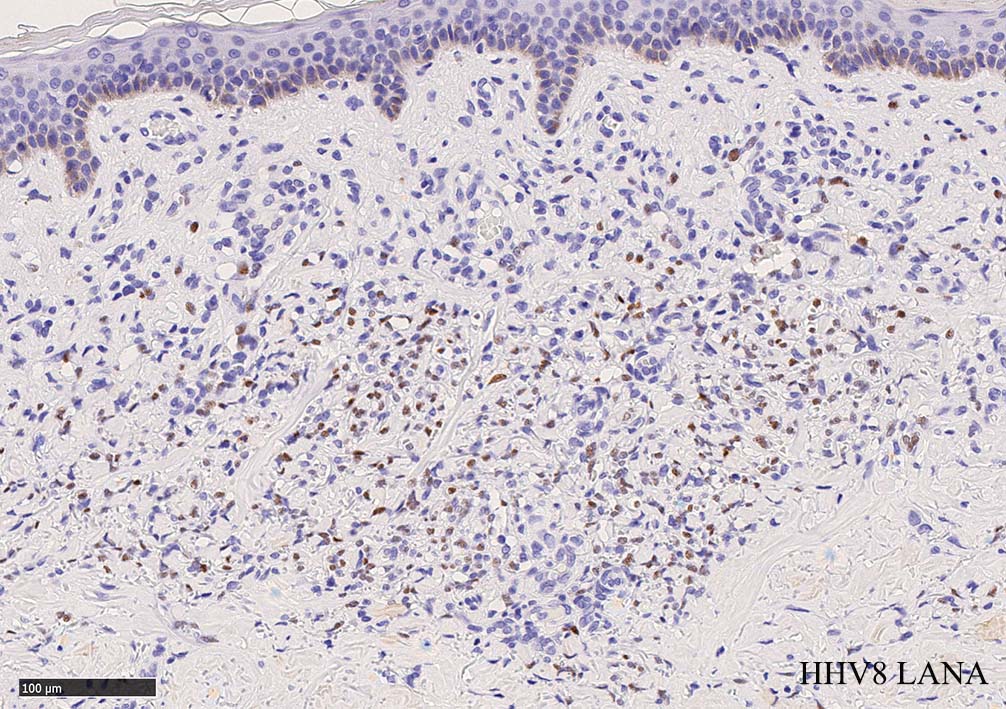

免疫染色, 分子病理学的検査

増生細胞はCd31, CD34, Factor Ⅷ, D2-40などが陽性を示す.

HHV-8の潜伏期関連抗原(HHV-8 Latency-associated nuclear antigen: HHV-8 LANA)が市販されており, 核が点状に染色される陽性所見がKaposi肉腫の確定診断に必須となっている.